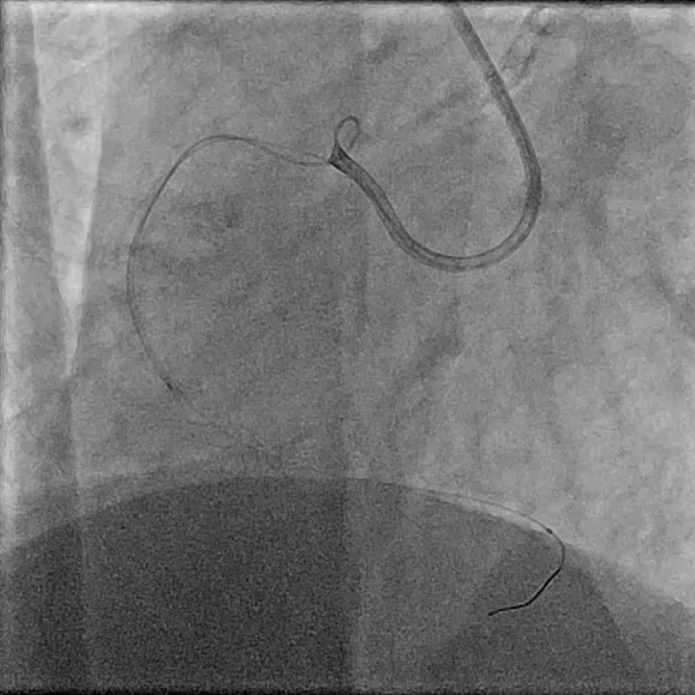

In view of severe left ventricular dysfunction, a 40cc IABP was inserted via the right common femoral artery for mechanical circulatory support during PCI. A 6Fr AL1 guide catheter was advanced via the right radial artery to selectively cannulate the right coronary artery (RCA). A Runthrough NS coronary guidewire was advanced into the distal R-PDA. Balloon angioplasty was performed from RPDA back to proximal RCA using a 2.5x15mm Sapphire3 NC balloon to 12atm. A Boston Scientific Opticross HD 60MHz IVUS catheter was advanced into the distal RPDA and intravascular imaging performed. Unfortunately, upon completion of the pullback run, the IVUS catheter could not be withdrawn. The IVUS catheter was stuck on the calcific and angulated segment in the proximal RPDA. Despite use of focused force technique, parallel ballooning, the IVUS catheter could not be withdrawn. During the attempts, the IVUS catheter inadvertently broke, leaving a short segment of the catheter in the RPDA. Check angiography showed no flow impairment. Thus, proximal to mid RCA was stented using a 3.0x38mm DES and a 3.5x48mm DES. Due to long procedural time, decision made to stage further PCI to the next day. The following day, PCI to LAD was performed uneventfully. The RCA was cannulated using a 7Fr AL2 guide catheter via right radial artery. A Sion Blue ES guidewire was advanced into the RPDA. A 6Fr Liquid guide extension catheter was advanced across the stented segments. A 3.2Fr EnSnare used to withdraw IVUS.

Case Summary

IVUS entrapment usually occurs on stent struts (distal edge, tortuous vessels, calcified lesions, small stent diameter). However, it can still happen in calcified and tortuous vessels. Follow the troubleshooting algorithm, do not forcibly pull. If the catheter breaks, can consider using such a snaring technique to retrieve. If all else fails, can perform CABG and removal of device.